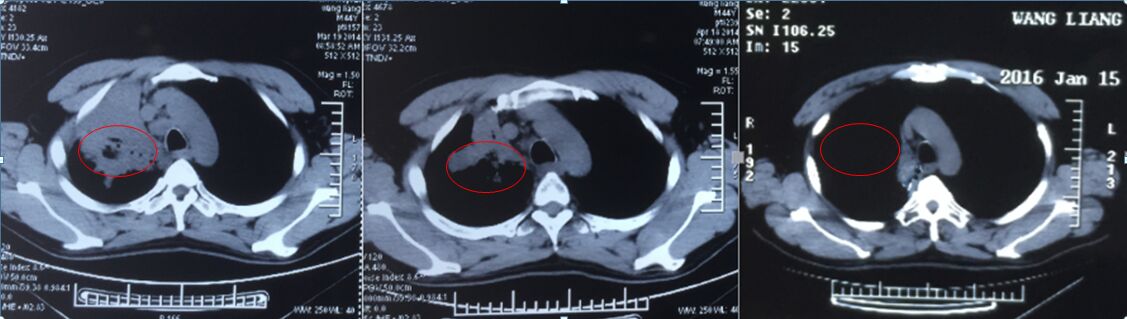

张先生接受A45动力和特异性免疫治疗 。治疗一个疗程后病灶明显缩小,治疗两年后,病灶几乎全部消退,目前患者状态良好,生活基本可以自理,可以做简单工作。

治疗前 治疗一个疗程 治疗两年后